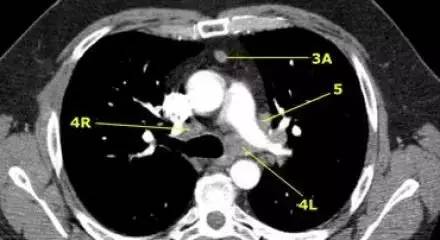

肺动脉干上 CT 横断面的左下气管旁淋巴结(4L)、右下气管旁淋巴结(4R)、血管前淋巴结(3A)、主动脉弓下淋巴结(5) 、奇静脉(蓝字)。

气管下段、隆突之上肺 CT 横断面的左下气管旁淋巴结(4L)、右下气管旁淋巴结(4R)、血管前淋巴结(3A)、主动脉弓下淋巴结(5)